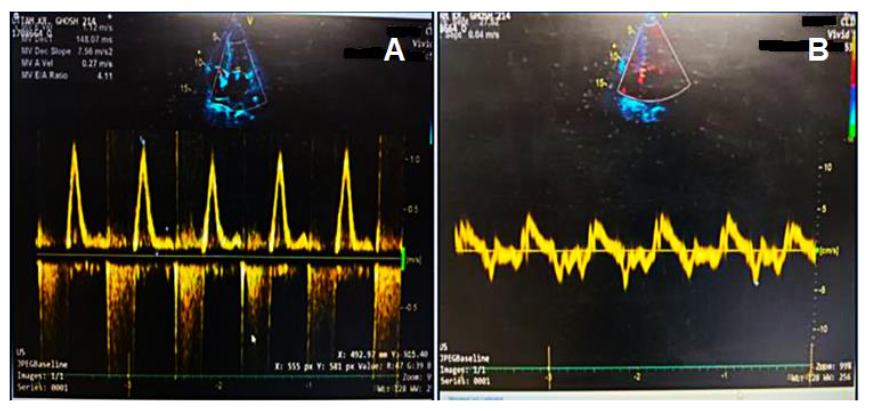

Figure 2: (a) Marked increase in early diastolic mitral inflow velocity with reduced late diastolic peak flow velocity and deceleration. (b) Decreased early diastolic mitral annulus velocity is shown.

Figure 2 shows the marked increase in early diastolic mitral inflow velocity.

The diagnostic workup demands integration of clinical findings with advanced imaging modalities, biochemical markers, and tissue biopsies. Key electrocardiographic findings include low voltage QRS complexes and left ventricular hypertrophy, while echocardiography can reveal hallmark red flags such as restrictive filling patterns and concentric hypertrophy.